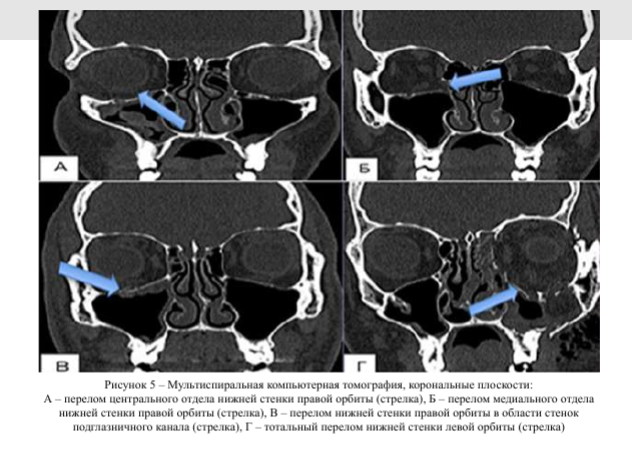

На рисунке 5 представлены результаты мультиспиральной компьютерной томографии переломов нижней стенки центрального отдела, медиального отдела, подглазничного канала правой орбиты и тотальный перелом нижней стенки левой орбиты в коронарной плоскости. Цель лечения, в частности, перелома нижней глазничной стенки - восстановление первоначальной формы и объема глазницы, репозиция ее содержимого и восстановление подвижности глазного яблока.